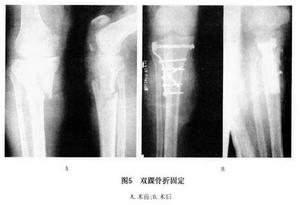

(6)脛骨平台骨折內固定:

④內外髁的T形和Y形骨折(Ⅳ型):復位操作方法用整復一側平台劈裂塌陷及劈裂塌陷折片相似,但先整復較重移位側平台的主要的骨折面,後整復較輕移位側平台的主要骨折片及其他較大的碎骨片,儘可能恢復平整的平台關節面。在移位重側用T形和L形鋼板固定,移位輕的一側用短鋼板固定。